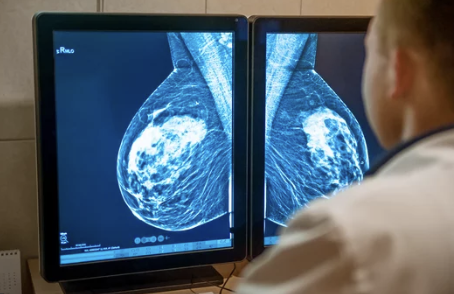

유방암 검사에는 유방 촬영술, 유방 초음파 검사, MRI 검사, 조직 검사 등 다양한 방법이 있습니다. 각 검사의 특징과 장단점을 이해하고, 전문의와 상담하여 자신에게 맞는 검사를 선택하는 것이 중요합니다.

- 유방 촬영술: X-ray를 이용하여 유방 조직을 촬영하는 검사입니다. 석회화 병변이나 종양을 발견하는 데 효과적입니다.

유방암은 조기에 발견하면 완치율이 매우 높습니다. 따라서 40세 이상 여성은 매년 유방 촬영술을 받는 것이 좋습니다. 고위험군에 속하는 경우에는 30세부터 정기적인 검진을 받는 것이 좋습니다.